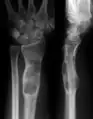

X-ray image showing enchondromas localized in the lower part of the radius of a 7-year-old girl with Ollier disease. | |

- X-ray showing enchondromas localized in the lower part of the radius of a 37-year-old patient affected with Ollier disease